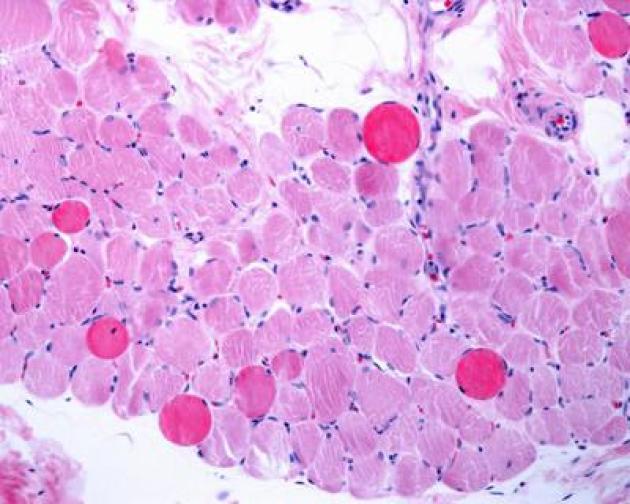

Roma, 4 nov. (Adnkronos Salute) - Sono positivi i risultati di un'analisi dei dati a lungo termine - comprese le prime valutazioni dello studio multicentrico in aperto Guardian, attualmente in corso - che valuta Agamree* (vamorolone) in pazienti affetti da distrofia muscolare di Duchenne (Dmd). Lo annuncia in una nota Santhera Pharmaceuticals, precisando che l'analisi ha incluso pazienti mai trattati con corticosteroidi e che hanno iniziato il trattamento con Agamree tra i 4 e i 7 anni di età nell'ambito di studi clinici, proseguendo poi attraverso vari programmi di accesso tra cui lo studio Guardian.

Sono stati analizzati i dati di un massimo di 110 pazienti, con un numero variabile in base alla disponibilità delle informazioni. In questa analisi i pazienti avevano ricevuto il trattamento per un massimo di 8 anni, con un follow-up mediano di circa 5 anni. La maggior parte dei pazienti ha mantenuto dosi elevate (4-6 mg/kg/giorno) in contesti clinici di real world durante il periodo di osservazione. I risultati mostrano che i pazienti trattati con vamorolone hanno mantenuto la funzione motoria durante il follow-up prolungato, dimostrando un'efficacia duratura del trattamento misurata in base al tempo di perdita della deambulazione paragonabile a quella dei corticosteroidi standard (p=0,91). Nelle analisi di sottogruppi prestabilite non sono state osservate differenze rispetto al deflazacort o al prednisone assunti quotidianamente. I dati - riporta l'azienda - continuano a confermare un profilo di sicurezza e tollerabilità differenziato rispetto ai corticosteroidi tradizionali. I pazienti trattati con Agamree hanno registrato un tasso significativamente inferiore di fratture vertebrali (p=0,0061), hanno mantenuto una crescita normale senza il rallentamento osservato con i corticosteroidi standard (p<0,0001) e hanno mostrato un numero inferiore di casi di cataratta rispetto ai pazienti trattati con glucocorticoidi, compresa un'incidenza notevolmente inferiore rispetto ai pazienti trattati con deflazacort (p<0,015). Inoltre, a oggi, non sono stati osservati casi di glaucoma. In media, le variazioni dell'indice di massa corporea o del peso, se rapportate all'altezza, non hanno mostrato differenze e non sono stati osservati nuovi segnali di sicurezza.